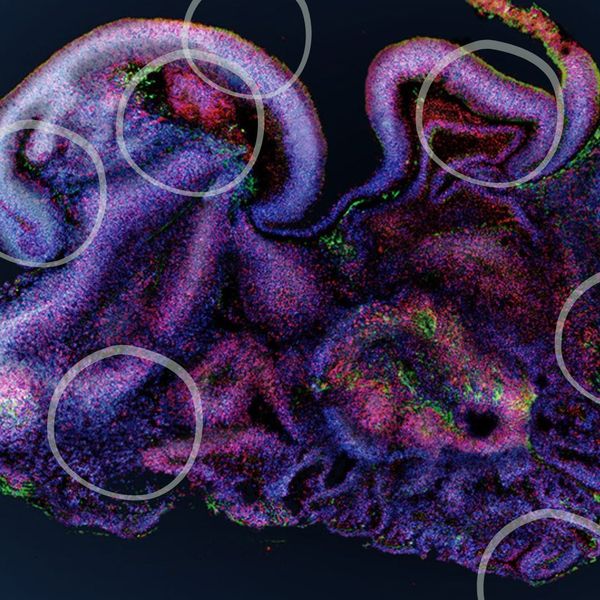

Image of necrotic cell death by Dr J.Skepper, Wellcome Collection (CC BY 4.0)

Could 3D Cell Cultures and Organoids Replace Animals in Research?

Animals have long been involved in the scientific research process, testing treatments and drugs to ensure they are safe for humans. This role animals play has been highly criticised due to ethical and welfare concerns. New research methods, such as 3D cell culture and organoid engineering have been explored as